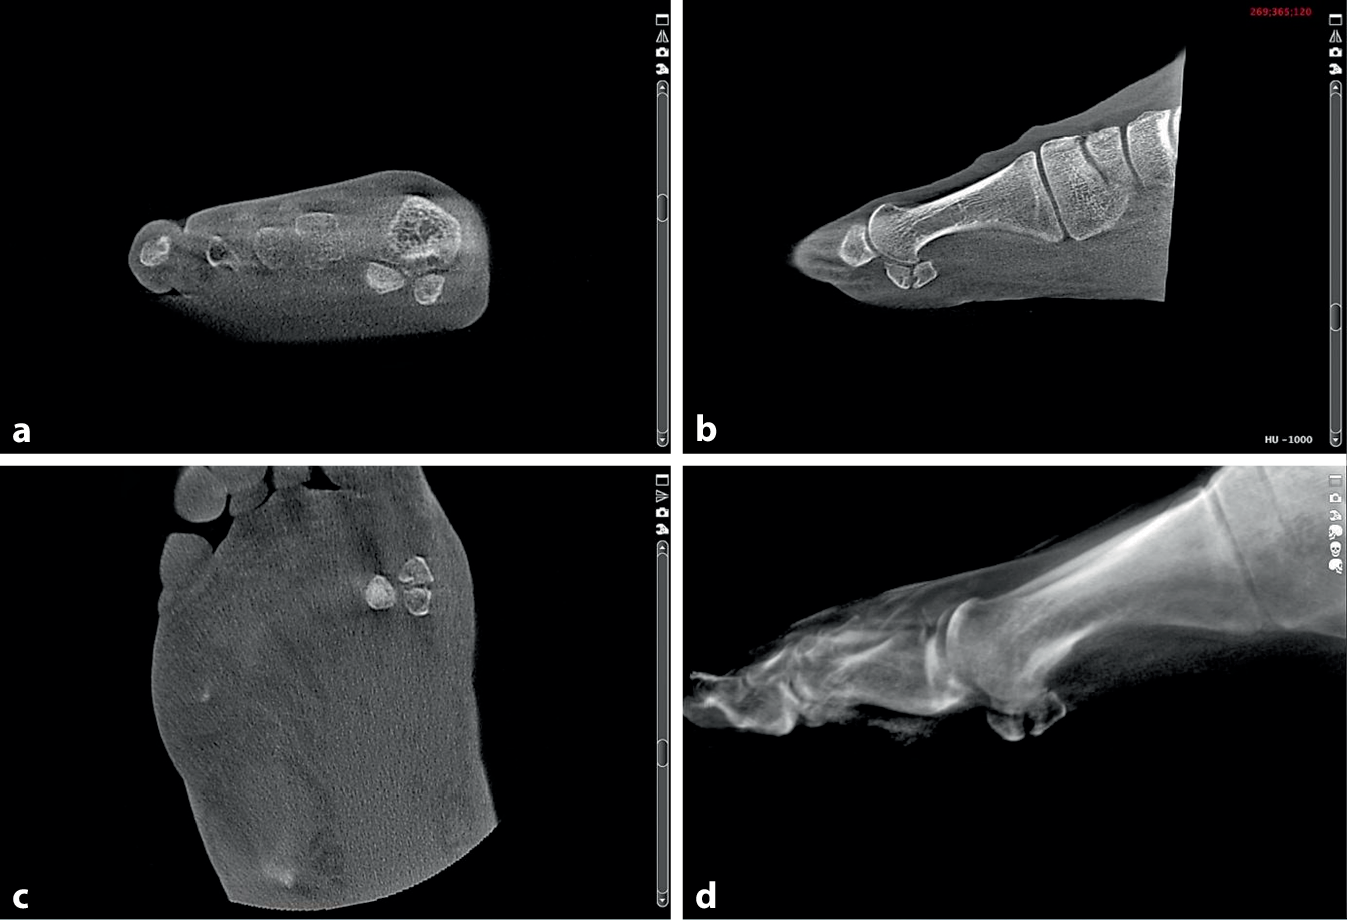

Die Magnetresonanztomographie (MRT) erscheint als diagnostisches Mittel der Wahl, insbesondere für das Knochenödem als Stressreaktion des Knochens. Eine Dünnschicht-Computertomographie (CT) bzw. die digitale Volumentomographie kann beispielsweise als Weight-bearing-CT (WBCT) bei Sesambeinfrakturen sehr hilfreiche Informationen liefern (Abb. 1).

Abb. 1

Weight-bearing-CT (WBCT) als digitale Volumentomographie im Stehen einer medialen Sesambeinfraktur in drei Ebenen (a-c) sowie in der dreidimensionalen Reformation (d)